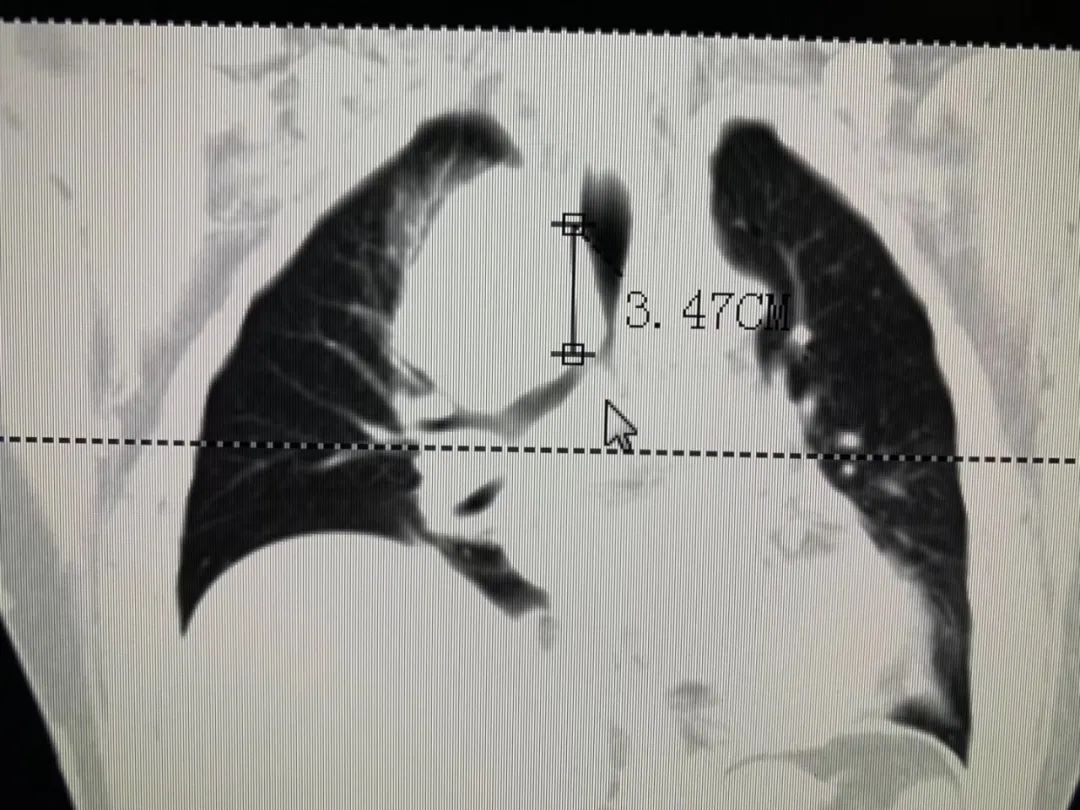

入院进行相关的检查,肺部CT检查结果显示:由于纵隔上的肿瘤压迫患者气管导致狭窄呼吸困难,找到张先生病灶原因后,牛院长带领医疗团队经过多次阅片、讨论,一致认为目前最先要解决的是困扰张大叔的呼吸问题,时间拖得越久就容易出现呼吸、心跳骤停的可能。

2020年4月8日,牛院长团队通过DSA+CT技术不仅快速准确找到狭窄的支气管,还更为清楚地看到肿瘤及其他周围组织的关系。在气管镜下,牛院长熟练进行着进导丝、送置入器、释放支架等等步骤;随后在微波射频消融设备下,将穿刺针刺入纵膈上的肿瘤部位,利用射频发热原理使肿瘤部位坏死。历时一个半小时手术顺利结束。